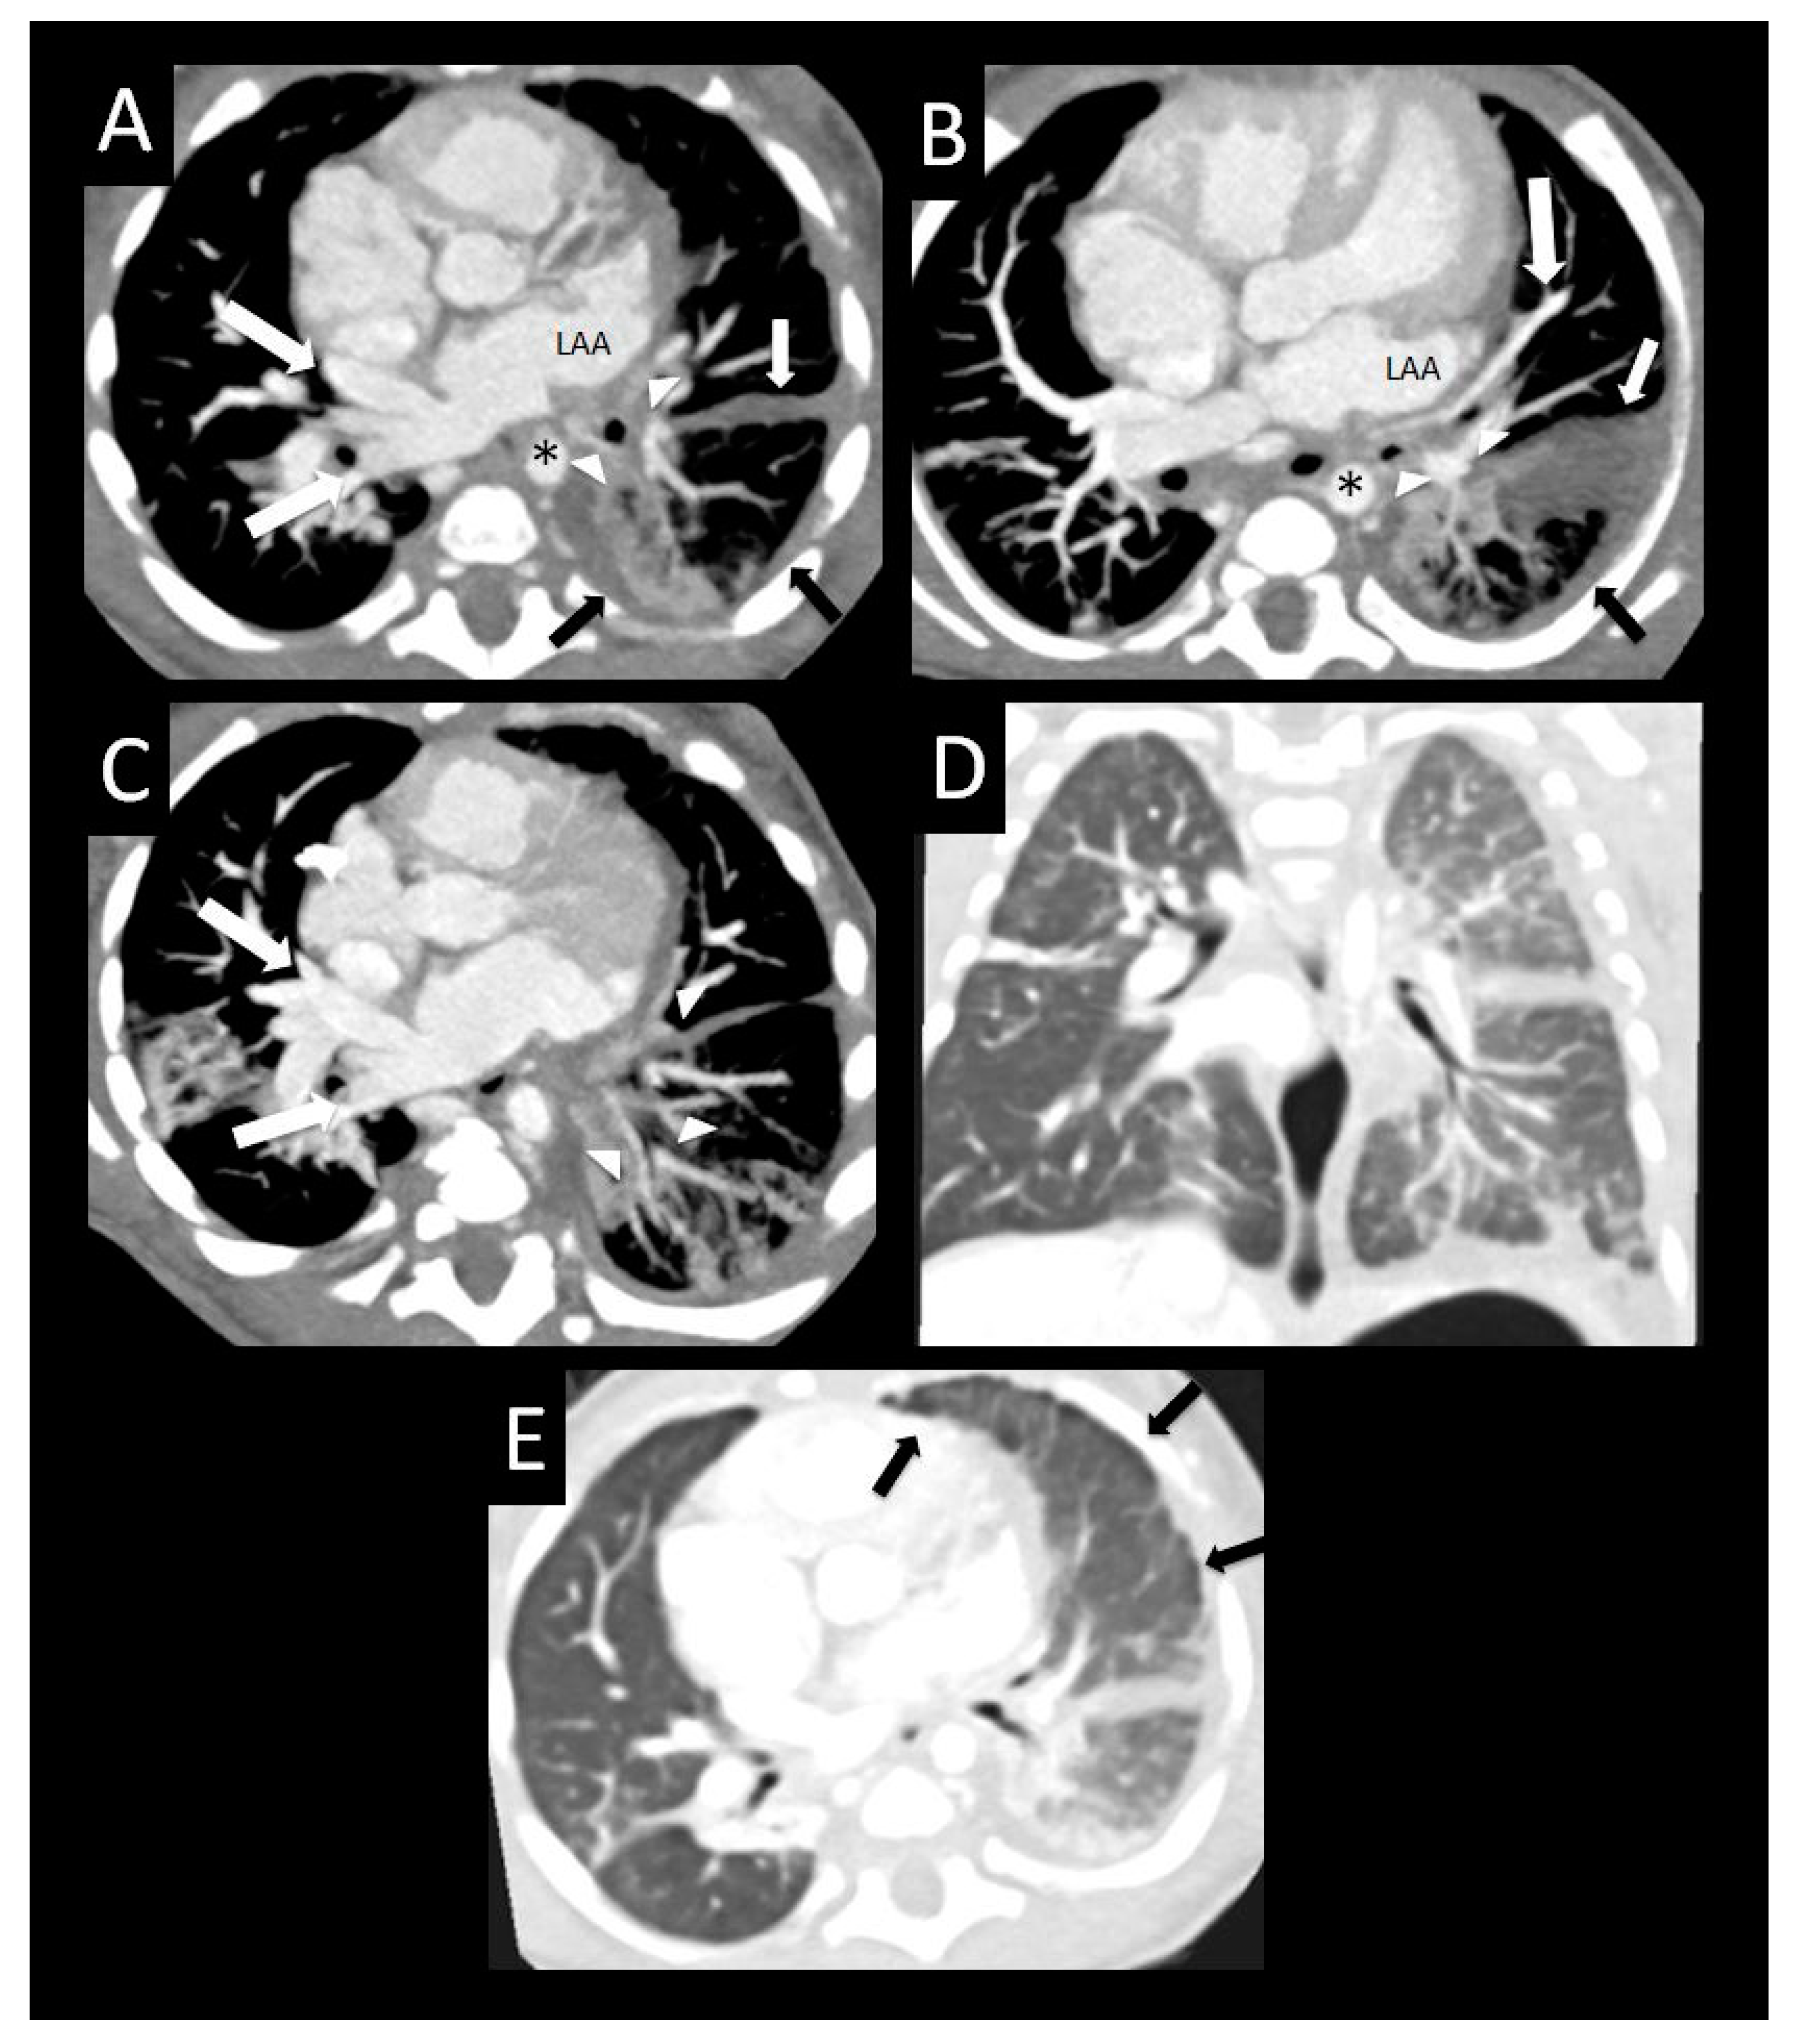

Figure 8. Ex-premature infant with pulmonary vein stenosis. Former 26-week premature infant with chronic lung disease, who underwent sutureless repair of PVS followed by left lower pulmonary vein stenting. Axial (A), sagittal (B), and coronal (C) images from a CTA performed 1 year later show left upper pulmonary vein atresia (large arrow (A,B)) in proximity to the dilated main pulmonary artery (MPA), with an enhancing interlobar collateral vessel coursing around the left pulmonary artery (arrowheads (A,B)), which connects to a cluster of vessels (small arrow (AC)). Another tortuous collateral (large arrow (C)) connects the cluster of vessels to the stented left lower pulmonary vein (*C). Coronal image (D) shows perihilar and mediastinal induration (*). Axial lung image (E) shows diffuse interlobular septal thickening, and a coronal minimum-intensity projection (F) image shows peripheral and intralobar tiny cysts (arrows (E,F)). The cysts do not correspond to lung segments most affected by PVS, and may be related to chronic lung disease.

The development of pulmonary venous collaterals would be expected to protect against lung damage due to pulmonary hypertension, as they divert pulmonary venous drainage to less obstructed veins. Although we found no significant relationship between the presence of pulmonary venous collaterals and death, our study may have been underpowered to demonstrate such a relationship. By CT, these collateral vessels can be seen as tortuous, abnormally arborizing vessels that cross pleural reflections to an adjacent lobe in the periphery of the lung (Figure 7). Alternatively, they may course around hilar structures more centrally (Figure 8A–C), or both (Figure 5). In addition, we observed mass-like clusters of tiny enhancing vessels between larger interlobar collateral vessels (Figure 5 and Figure 8). These clusters of tiny vessels tend to be located adjacent to pleural reflections, and resemble small areas of consolidation on lung reconstructions. However, the vascular enhancement of these lesions is well visualized on soft tissue reconstructions. These lesions may represent the CT correlate of hemangioma-like foci, which have been found at pathology in patients with PVS [12].

Notably, we found that perihilar induration (Figure 8) was associated with a lower hazard of death. We hypothesize that the perihilar induration, mediastinal induration, and diffuse pleural thickening associated with PVS on CT could reflect manifestations of secondary lymphatic proliferation and increased lymphatic drainage of edematous lung, which may have a relative protective effect. The lymphatic drainage of the lung is primarily along peribronchovascular bundles and pleural lymphatics, which drain to the central lymphatics of the mediastinum. The pulmonary lymphatic system provides clearance of interstitial fluid and is a necessary component of postnatal pulmonary function. Furthermore, lymphatic development is thought to continue postnatally through sprouting of new vessels from existing lymphatic vessels or circulating progenitor lymphatic endothelial cells [19]. Lymphatic abnormalities such as pulmonary lymphangiectasia have been documented in 50% of lung biopsies in patients undergoing surgical repair of PVS, suggesting that abnormalities involving the lymphatic system are widespread in this disease [12].

Central intraparenchymal and peripheral lung cysts were found in patients with severe PVS with atresia (Figure 10 and Figure 12), reflecting severe lung damage and fibrosis. Similar to other pulmonary findings in PVS, cysts are also nonspecific and can be seen in other forms of pulmonary disease such as chronic lung disease (Figure 8 and Figure 9), pulmonary interstitial glycogenosis, primary surfactant deficiency disorders in term infants, and certain genetic conditions such as Trisomy 21 [20,21]. Therefore, the distribution of lung cysts and knowledge of any underlying confounding conditions must be considered before lung cysts can be attributed to lung damage associated with PVS.

Incidentally, several of the CT studies also exhibited scattered hyperlucent lobules throughout the lung parenchyma, which we believe is related to prematurity rather than PVS (Figure 6E,F and Figure 8). Chronic lung disease of prematurity, or bronchopulmonary dysplasia, is an alveolar growth disorder characterized by hyperlucent lobules of the lung that have decreased vascularization, which results from alveolar enlargement and simplification as well as interstitial fibrosis with interlobular septal thickening [20]. The known association between prematurity and development of PVS increases the likelihood that some patients had both chronic lung disease of prematurity, and other classic pulmonary findings of PVS [17]. Hyperlucent lobules, therefore, should not be confused with other more characteristic pulmonary findings in PVS described above.